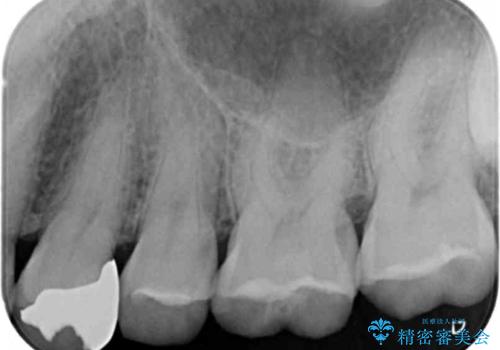

- 奥歯の詰め物のやり替え希望で来院されました。

残る歯の量が多かったためすべてインレーでの治療となりました。

- 左上4567 セラミックインレー 7,7000円×4本 費用は治療当時の料金となります

この方は詰め物が割れてしまうのを防ぐためにナイトガードも作成しました。